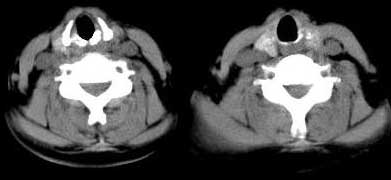

女 48岁 无意中发现左侧颈部肿块

甲状腺左侧叶下部结节状低密影,边界较清晰,考虑甲状腺肿瘤[腺瘤可能性大,恶性待排]

甲状腺左叶低密度病灶,边界尚清楚,邻近气管、血管、肌肉无明显侵润;考虑良性病灶,以甲状腺腺瘤可能大。

左侧甲状腺下极可见类圆形结节样低密度病灶,边缘清晰,未见明显周围组织受侵,颈部未见明确淋巴结肿大;右侧甲状腺形态密度未见异常。

诊断意见:左侧甲状腺结节样病灶,多考虑甲状腺腺瘤。建议ect检查。